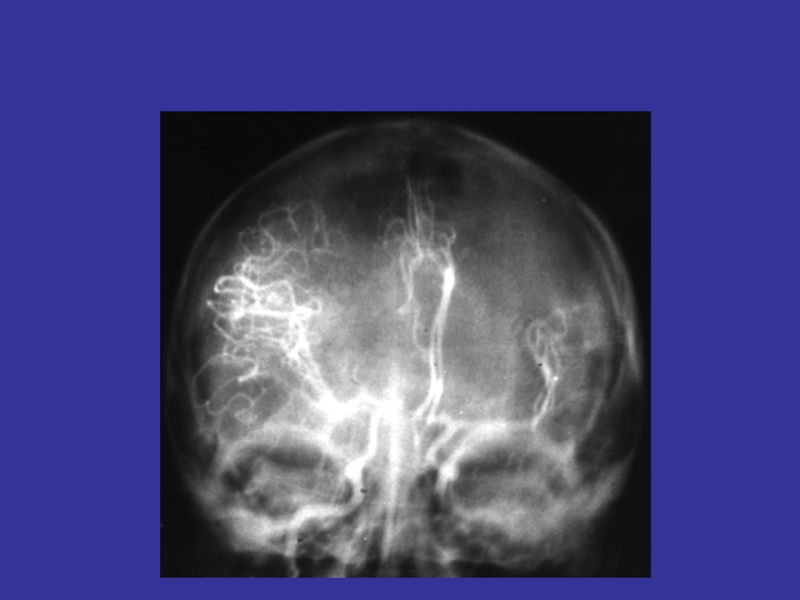

Слайд 102Ангиографические признаки

внутримозговой гематомы

Ангиографические признаки внутримозговой гематомы

Слайд 101Ангиографические признаки

Бессосудистая зона

Смещение ПМА

Смещение СМА

Ангиографические признаки внутримозговой гематомы Бессосудистая зона Смещение ПМА Смещение СМА